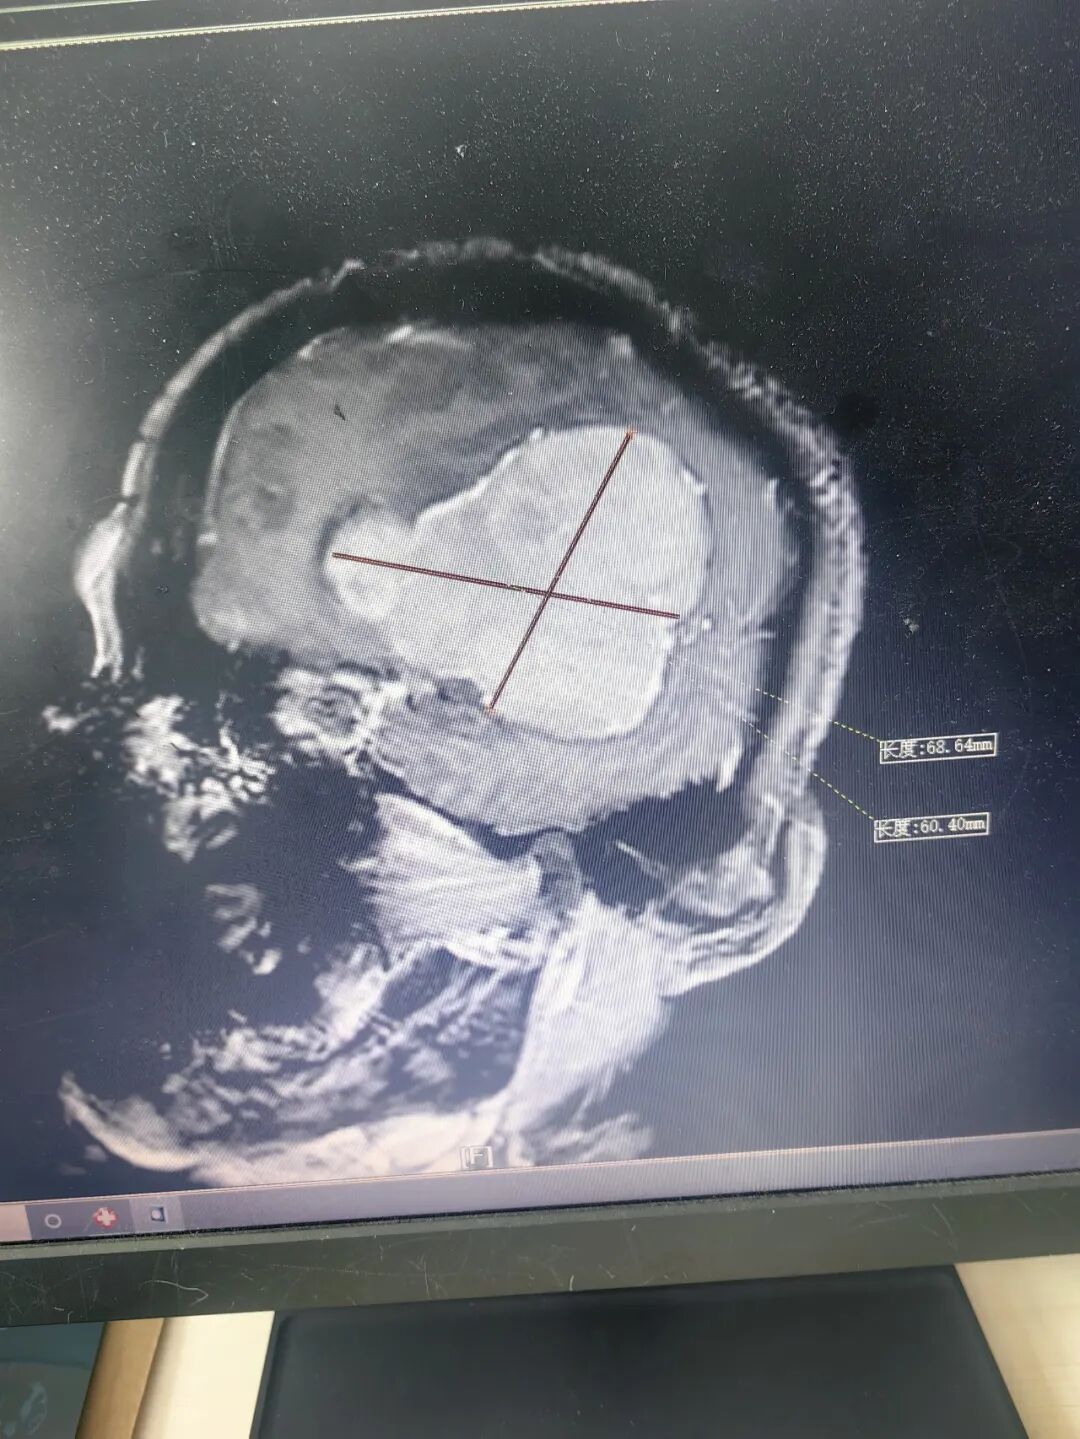

为确保万无一失,医院组织神经外科、麻醉科、重症医学科(ICU)等多学科专家进行了详尽的术前讨论,制定了周密的手术方案及应急预案。手术当天,神经外科团队在手术麻醉科的密切配合下,顺利为患者实施“左侧脑肿瘤切除术”。手术过程顺利,出血控制理想。术后,患者被立即转入ICU进行密切监护。

术后影像

图片

在ICU团队的精心治疗与护理下,患者神志恢复清楚,四肢活动自如,无偏瘫等严重并发症,术后第6天病情趋于平稳。